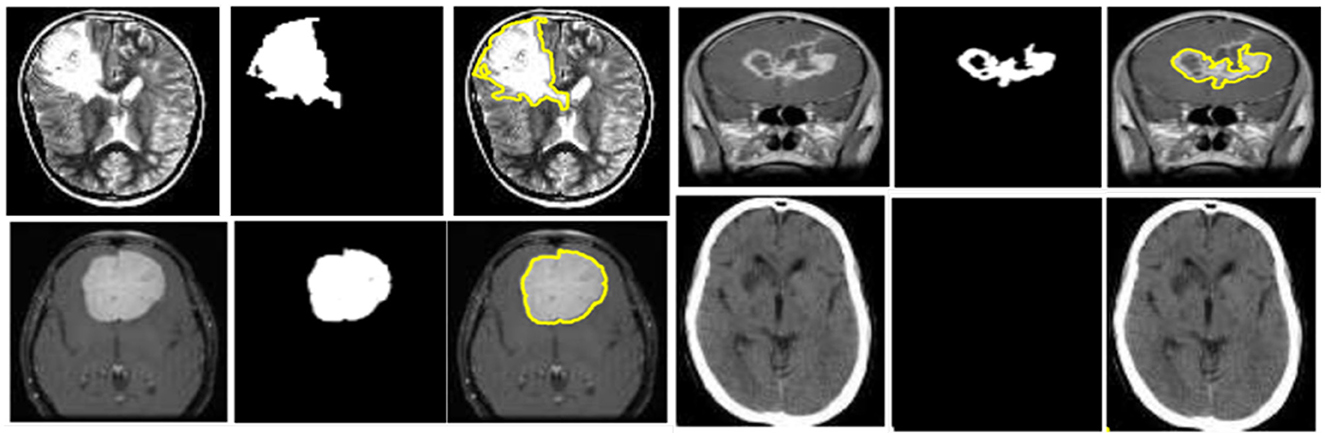

GAME-Net: An Ensemble Deep Learning Framework Integrating Generative Autoencoders and Attention Mechanisms for Automated Brain Tumor Segmentation in MRI

Computational approaches that unite Artificial Intelligence (AI), Machine Learning (ML), and biomedical imaging are transforming the landscape of life sciences research. Brain tumors require accurate and early detection for effective treatment planning. Manual segmentation of Magnetic Resonance Imaging (MRI) is time-consuming and prone to variability. This study proposes an advanced deep learning framework integrating Generative Autoencoders with Attention Mechanisms (GAME), Convolutional Neural Networks (CNNs), and U-Net-based architectures for automated brain tumor segmentation. The model enhances feature extraction, tumor localization, and classification accuracy. Using 5,880 MRI images, divided into training, validation, and test sets, preprocessing involved intensity normalization, data augmentation, and unsupervised feature extraction based on the BraTS 2023 benchmark dataset, accessed through the Kaggle distribution portal to ensure consistency with established brain tumor segmentation standards. Segmentation leverages U-Net with attention, while classification employs CNN and Transformer-based self-attention. The generative autoencoder improves feature representation by learning tumor-specific patterns. The framework outperformed traditional models, achieving a Dice Coefficient of 0.85, Jaccard Index of 0.78, Accuracy of 87.18%, Sensitivity of 88.3%, Specificity of 86.5%, and AUC-ROC of 0.91. By demonstrating how advanced computational modelling and unsupervised feature learning can address clinically relevant challenges, this work exemplifies the integration of AI and data science within the biomedical domain.